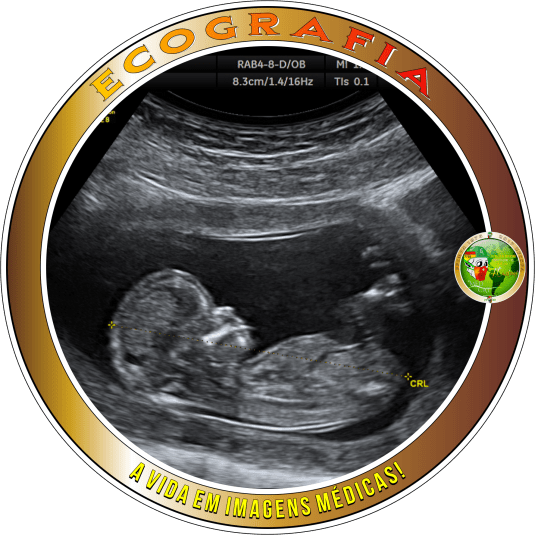

Ecografia * Medicina * Especialidades Médicas